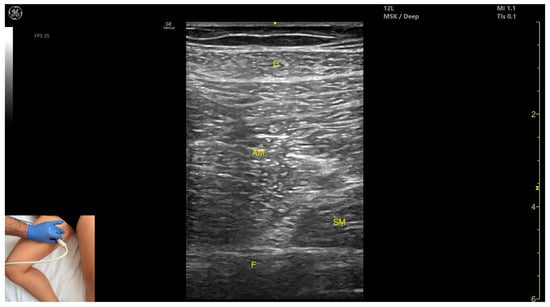

3.6. Gracilis (G)

3.6.1. Overview

3.6.2. Ultrasound Identification

3.6.3. Key Ultrasound Landmarks

- Muscle position: It is the most superficial and medial muscle mass of the thigh. Lateral and deep to the G lies the adductor longus, while medial and deep to the G lies the semimembranosus.

- External fascia: It presents a well-defined fascia that separates it from the subcutaneous plane and from the adductor magnus, adductor longus, and semimembranosus, which is relevant for BoNT-A injections.

- Dynamic evaluation: During dynamic evaluation, scanning toward the distal third of the medial thigh, the following are observed: the relationship between the G and adductor magnus remains consistent, the adductor longus disappears from view, the Sart muscle appears, joining the gracilis, and the adductor canal becomes visible, located deep and lateral to the gracilis. In the distal third of the medial thigh, the G is positioned lateral to the semitendinosus. Scanning further distally beyond the knee joint, the tendons of the G, sartorius, and semitendinosus converge to form the pes anserinus on the medial aspect of the proximal tibia. Muscle contraction is visible during hip adduction, knee flexion, and internal rotation maneuvers.

3.6.4. Clinical Implications and Injection Strategy

3.8. Adductor Magnus (AM)

3.8.1. Overview

3.8.2. Ultrasound Identification

3.8.3. Key Ultrasound Landmarks

- Muscle morphology: It is the largest and deepest muscle of the adductor group.

- Muscle position: It is the first muscle mass superficial to the femoral cortex at this level. It is covered superficially by the gracilis muscle; medial to it lies the semimembranosus.

- External fascia: It has a well-defined fascia separating it from the gracilis and semimembranosus, supporting safe BoNT-A injections.

- Dynamic evaluation: During dynamic evaluation, scanning distally toward the knee joint, a reduction in muscle bulk is observed in both the AM and gracilis. Muscle contraction is visible during hip adduction and hip flexion maneuvers.

3.8.4. Clinical Implications and Injection Strategy